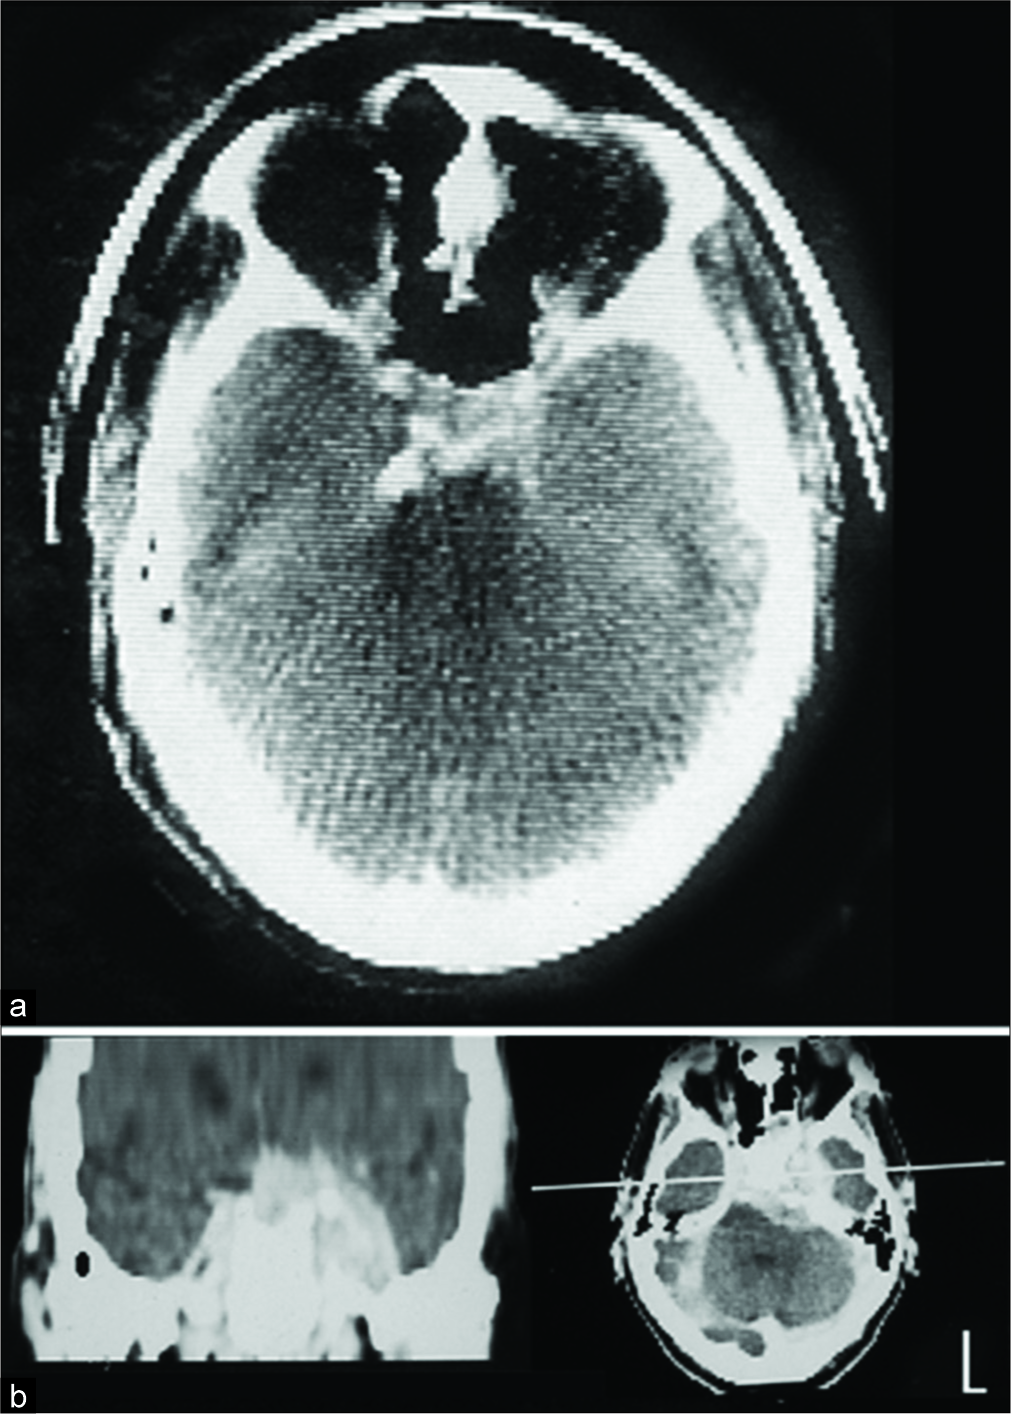

轻微的眼睑下垂通过眼镜上的一个小装置得以矫正,他得以继续他的牙医工作。1976年,当时被称为电学和音乐工业(EMI)的扫描显示,蝶鞍外侧有一处不易解释的病变[图1a],因此继续进行保守治疗。6年后,他出现了完全性3神经麻痹和左眼闭合,计算机断层扫描(CT)显示明显的CSM证据[图1b]。他还出现了部分半月形失明。虽然他不介意左眼的损失,因为眼睛是闭着的,但保守的治疗似乎不再合理。尽管存在一些慢性肺部疾病,但在1983年,医生建议只切除压迫交叉和右视神经的那部分肿瘤,他接受了手术。这使右眼的视野恢复到接近正常。为了保持视力,他接受了放射治疗。他的视力一直保持稳定,直到5年后,即复视28年后,他死于不相关的原因,享年83岁。

图1